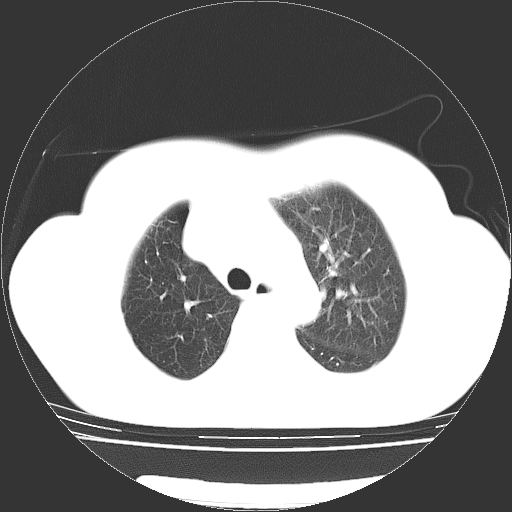

以下是引用zhangzhongshou在2008-3-22 12:52:00的发言:[br]1、右侧液气胸。[br]2、腹水。建议进一步检查。

以下是引用鲁巨ct在2008-3-22 14:10:00的发言:[br]1、右侧液气胸,右中下叶节段性不张。[br]2、腹水,建议上腹部ct检查

以下是引用zjzjr在2008-3-22 17:19:00的发言:[br]1、右侧液气胸,右下叶节段性不张。[br]2、腹水,建议上腹部ct检查